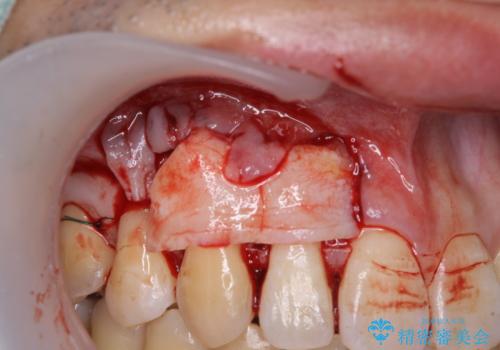

八重歯の歯根が見えている点も気になっているので、矯正歯科治療後に歯肉移植による根面被覆を行うこととしました。

矯正治療により元々気になっていた八重歯と、反対咬合が改善された歯の2本に対して根面被覆を行い、審美面の改善も達成しました。

- 外科手術のため、術後に痛みや腫れ、違和感を伴います